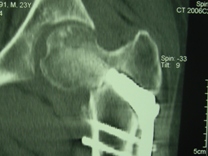

Уважаемые коллеги, приношу извинения за перерыв в работе -

был в командировке. За это время больному сделали КТ и,  сегодня,

снимки. Укорочение конечности - 1-1,5 см, ШДУ-115 градусов, замедленная консолидация,

остеопороз.

Вопрос о тактике дальнейшего ведения пациента (напоминаю, возраст 19

лет)?